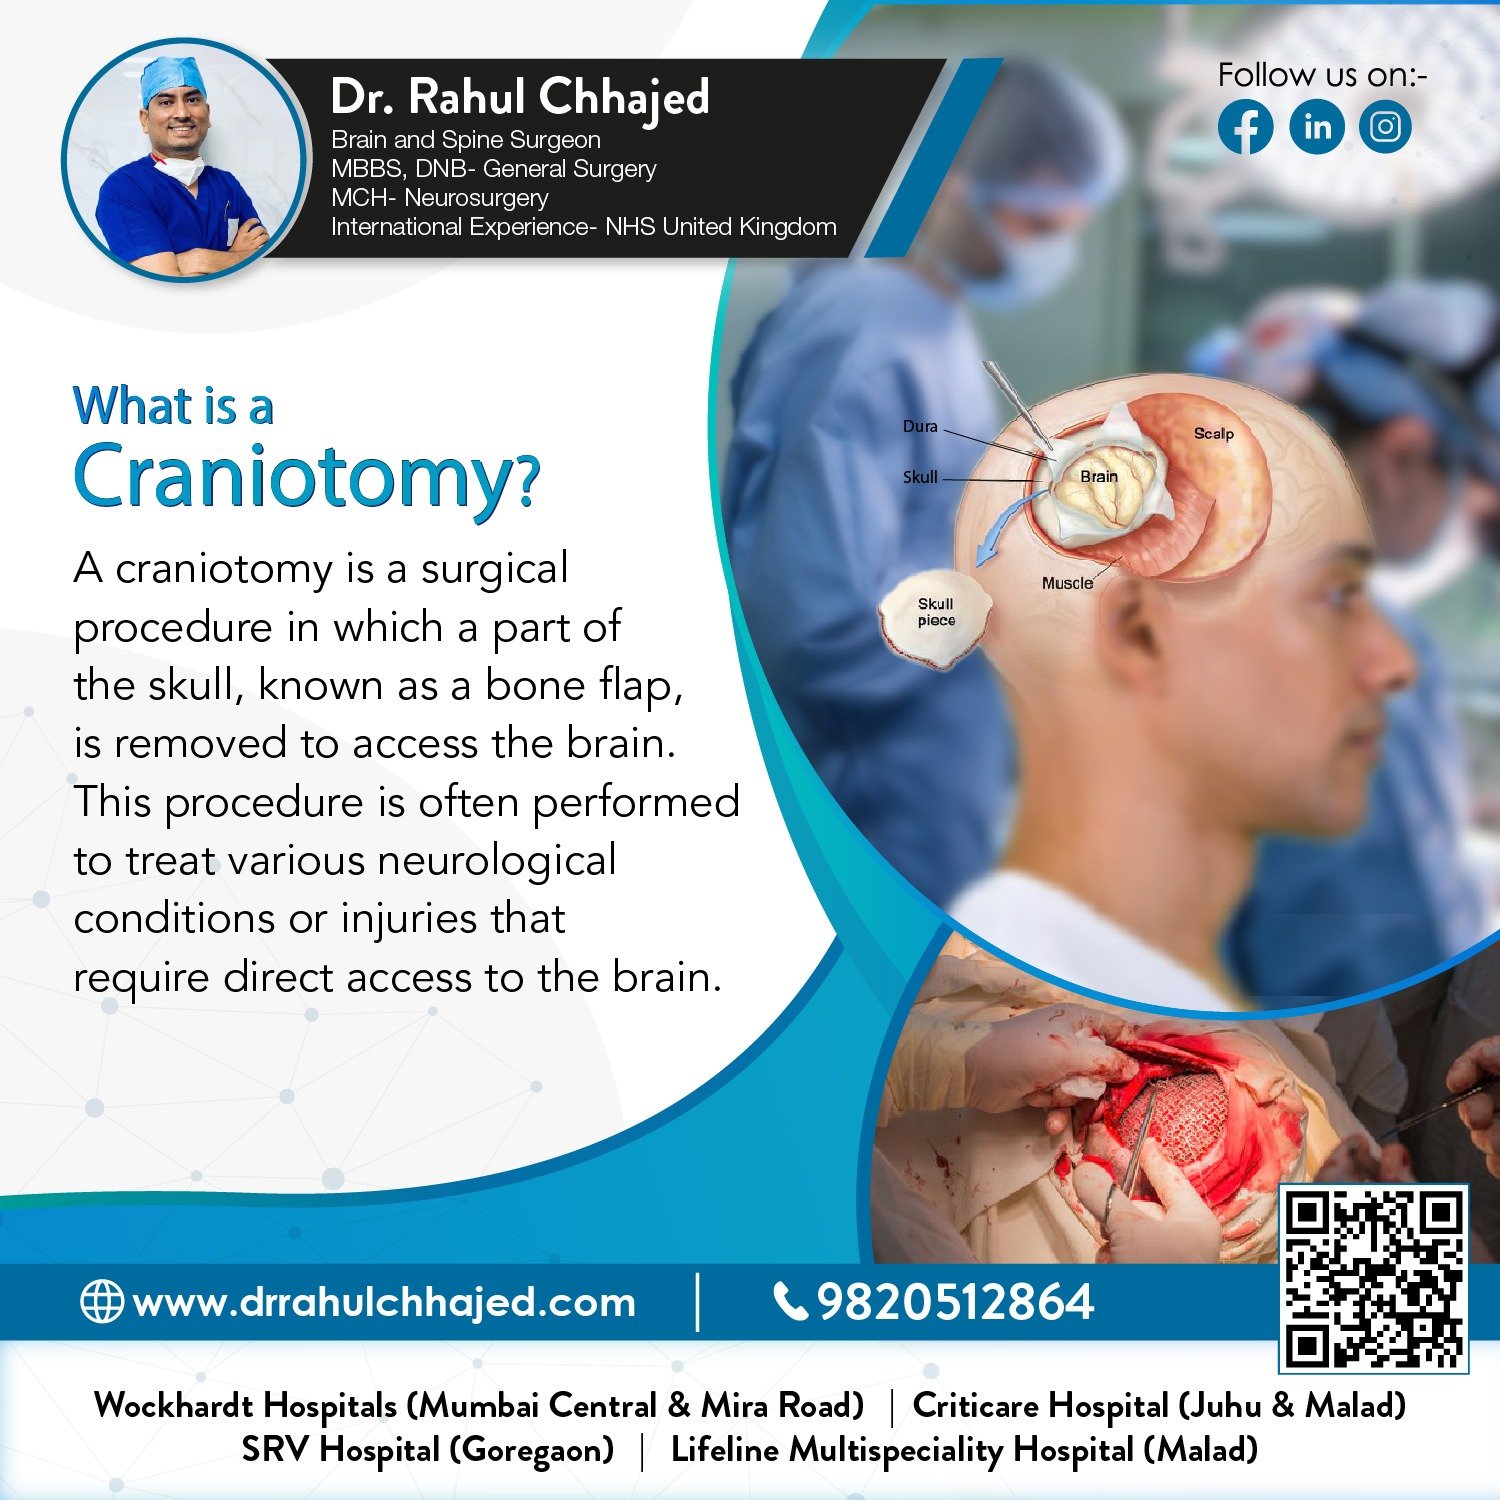

Hydrocephalus Surgery

The most common treatment for hydrocephalus is the surgical insertion of a drainage system, called a shunt. At our practice, we specialize in hydrocephalus surgery, which can relieve the pressure on the brain and help alleviate symptoms.